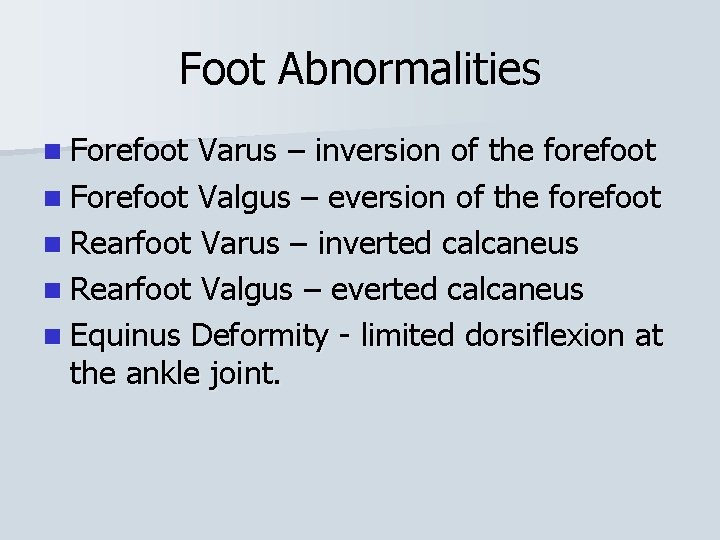

Foot Abnormalities n Forefoot Varus – inversion of the forefoot n Forefoot Valgus – eversion of the forefoot n Rearfoot Varus – inverted calcaneus n Rearfoot Valgus – everted calcaneus n Equinus Deformity - limited dorsiflexion at the ankle joint.